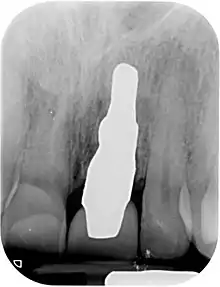

RAIs are custom made to perfectly fit the tooth socket of a specific patient immediately after tooth extraction. Therefore every implant is unique. As an optimized root-form it is much more than a simple 1:1 replica of a tooth. Since it exactly fills the gap left after the tooth is extracted, surgery is rarely needed. The implant can be produced from a copy of the extracted tooth, an impression of the tooth socket, or from a CT scan or CBCT scan.[3] The advantage of a CBCT scan is that the implant can be produced before extraction. With the former methods, it takes one or two days to fabricate an implant.

A root analogue implant can be fabricated from zirconium dioxide (zirconia) or titanium. Successful titanium RAIs have been three-dimensionally printed as porous one-piece implants, using CAD software.[4] However, zirconia is the preferred material, because it is more esthetic in color, with no grey discoloration visible through gums.[5][1]